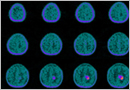

교모세포종

교모세포종은 4등급의 성상세포종(별세포종)으로 성상세포종 중에서 가장 악성이며 조직학적으로는 역형성 성상세포종에 괴사소견이 추가된 것입니다. 이 종양은 가장 흔한 악성 원발성 뇌종양으로 성인 신경교종의 1/4, 소아 신경교종의 15%를 차지하며 소뇌에 발생하는 경우는 흔치 않은 것으로 보고되고 있습니다